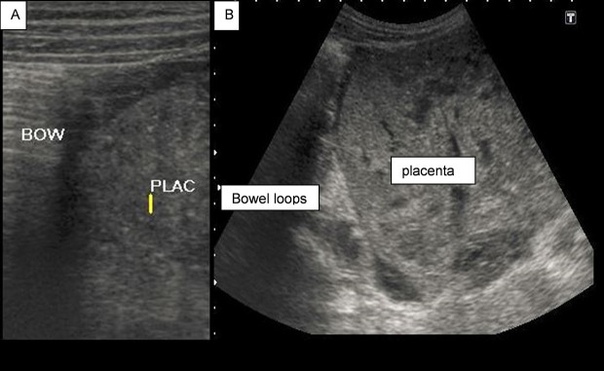

Жалобы на заложенность в ушах. Ранее у пациентки была выявлена ретркация барабанной перепонки, рекомендовано выполнять пользу Вальсальвы, что временно уменьшало ощущение заложенности.

В течение 6 лет пациентка выполняла упражнение 4 раза в день ежедневно.

При осмотре: в толще барабанных перепонок пузырьки воздуха, признаков отека или воспаления нет. Аудиография: умеренная кондуктивная тугоухость справа, нормальный слух слева.

Вероятнее всего изменения барабанных перепонок вызваны за счет частого выполнения пробы Вальсальвы.

Рекомендовано снизить интенсивность и частоту выполнения пробы.

При осмотре спустя 1 месяц отмечено улучшение.